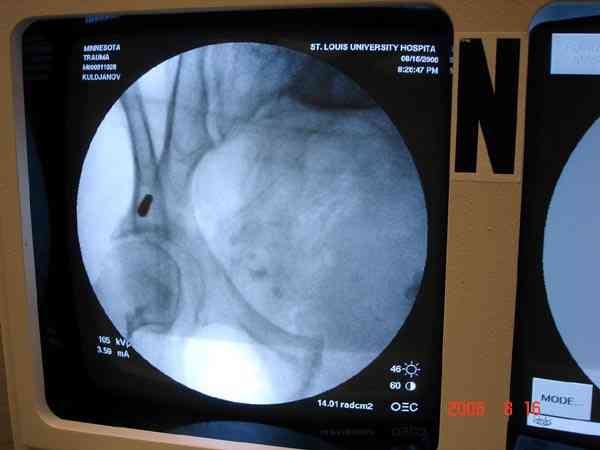

Прооперировали молодую девушку 32 лет спустя 9 мес после травмы. Имелся стойкий болевой синдром, неопороспособность левой н/конечности, моторные и сенсорные нарушения в левой голени и стопе, патологическая подвижность левой половины таза. Первым этапом закрыто в аппарате исправили деформацию ( в течении 2,5 нед). Вторым закрытое введение илиосакральных винтов в крестец (канюллированные 7,2 мм Chm) + туннелизация зоны псевдоартроза спицама Киршнера, реконструкция передних отделов таза, накостный остеосинтез . Аппарат частично демонтирпован, оставлена "передняя рама" После устранения деформации отмечен регресс неврологической симптоматики, уменьшение болевого синдрома. Интересующие вопросы: 1. Прогноз для сращения псевдоартроза крестца. 2. сроки нагрузки весом левой половины таза. Буду очень признателен за ваши мнения по этому поводу.A female 32 y.o. admitted to our unit 9 months after initial injury with pain, inability to bear weight at the left lower limb, sensor and motor disturbances in the left foot and tibia, with mobility of the left hemipelvis.At first closed reduction was performed by an external fixator within 2,5 weeks. After correction her pain decreased and some neurological progress was achieved. Now two iliosacral screws 7,2 mm were inserted, and anterior lesion was fixed by a plate. External fixator was partially unmounted, only anterior frame left in place.Images attached.How would you evaluate chances of healing of the sacrum with the current position?When would you allow weight-bearing of the left leg?THX in advance.